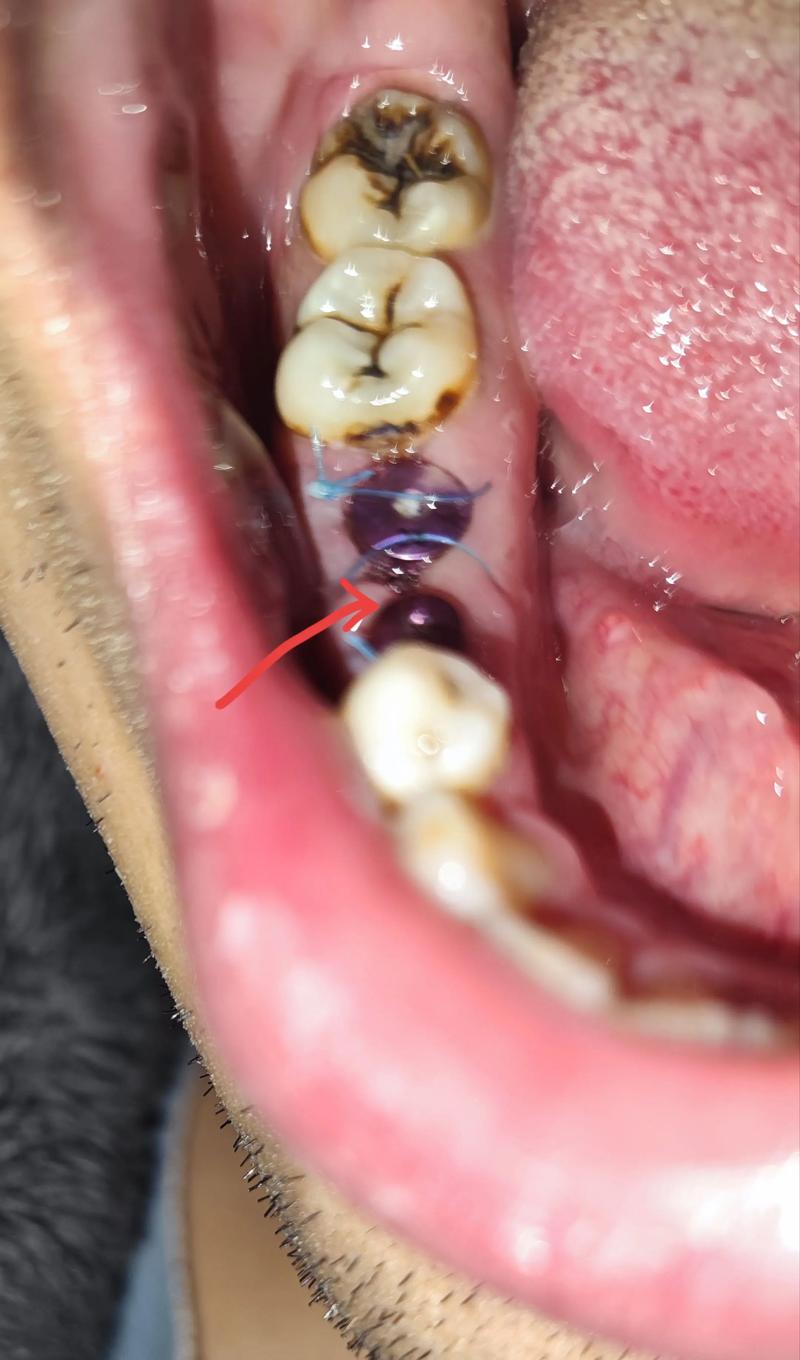

尽管可吸收缝线设计为“自行消失”,但临床中仍可能出现线头外露或刺激反应(如局部红肿、异物感),此时需由医生评估:若线头较短且无不适,可观察等待其自然吸收;若线头过长或引发炎症,医生会通过无菌操作剪除多余部分,无需“全程拆线”。